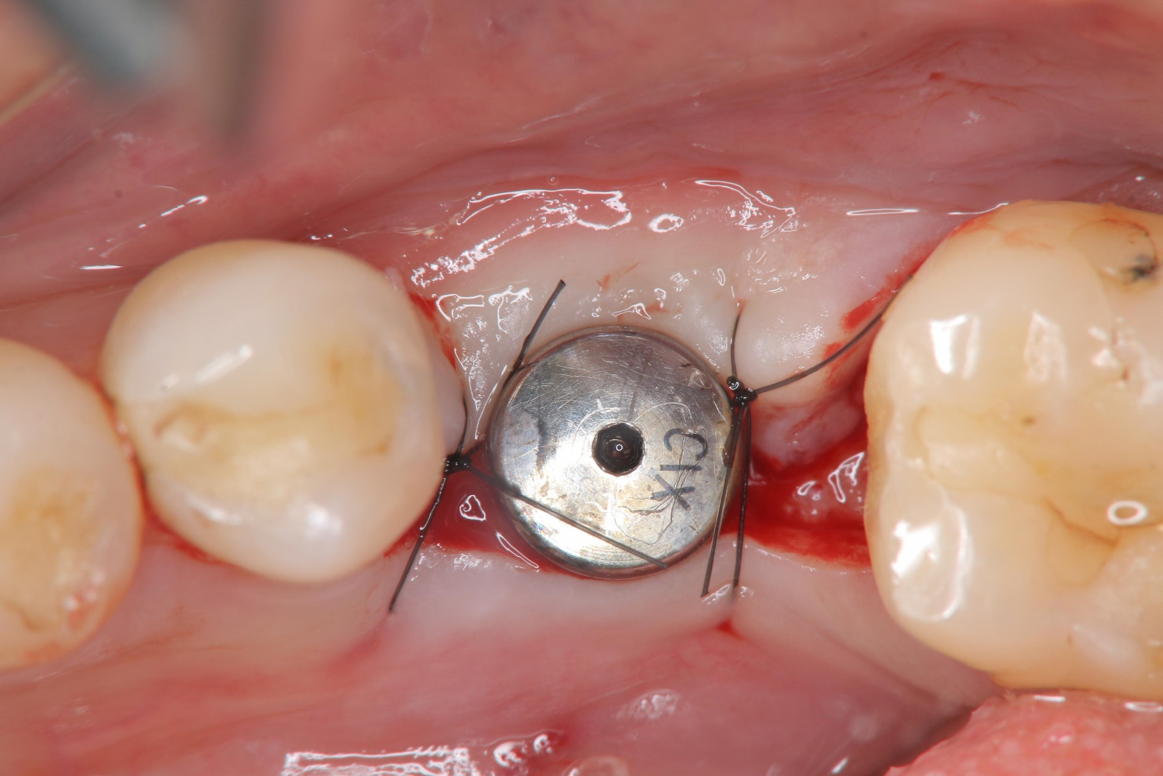

上顎植牙二階手術

臨床照相比色